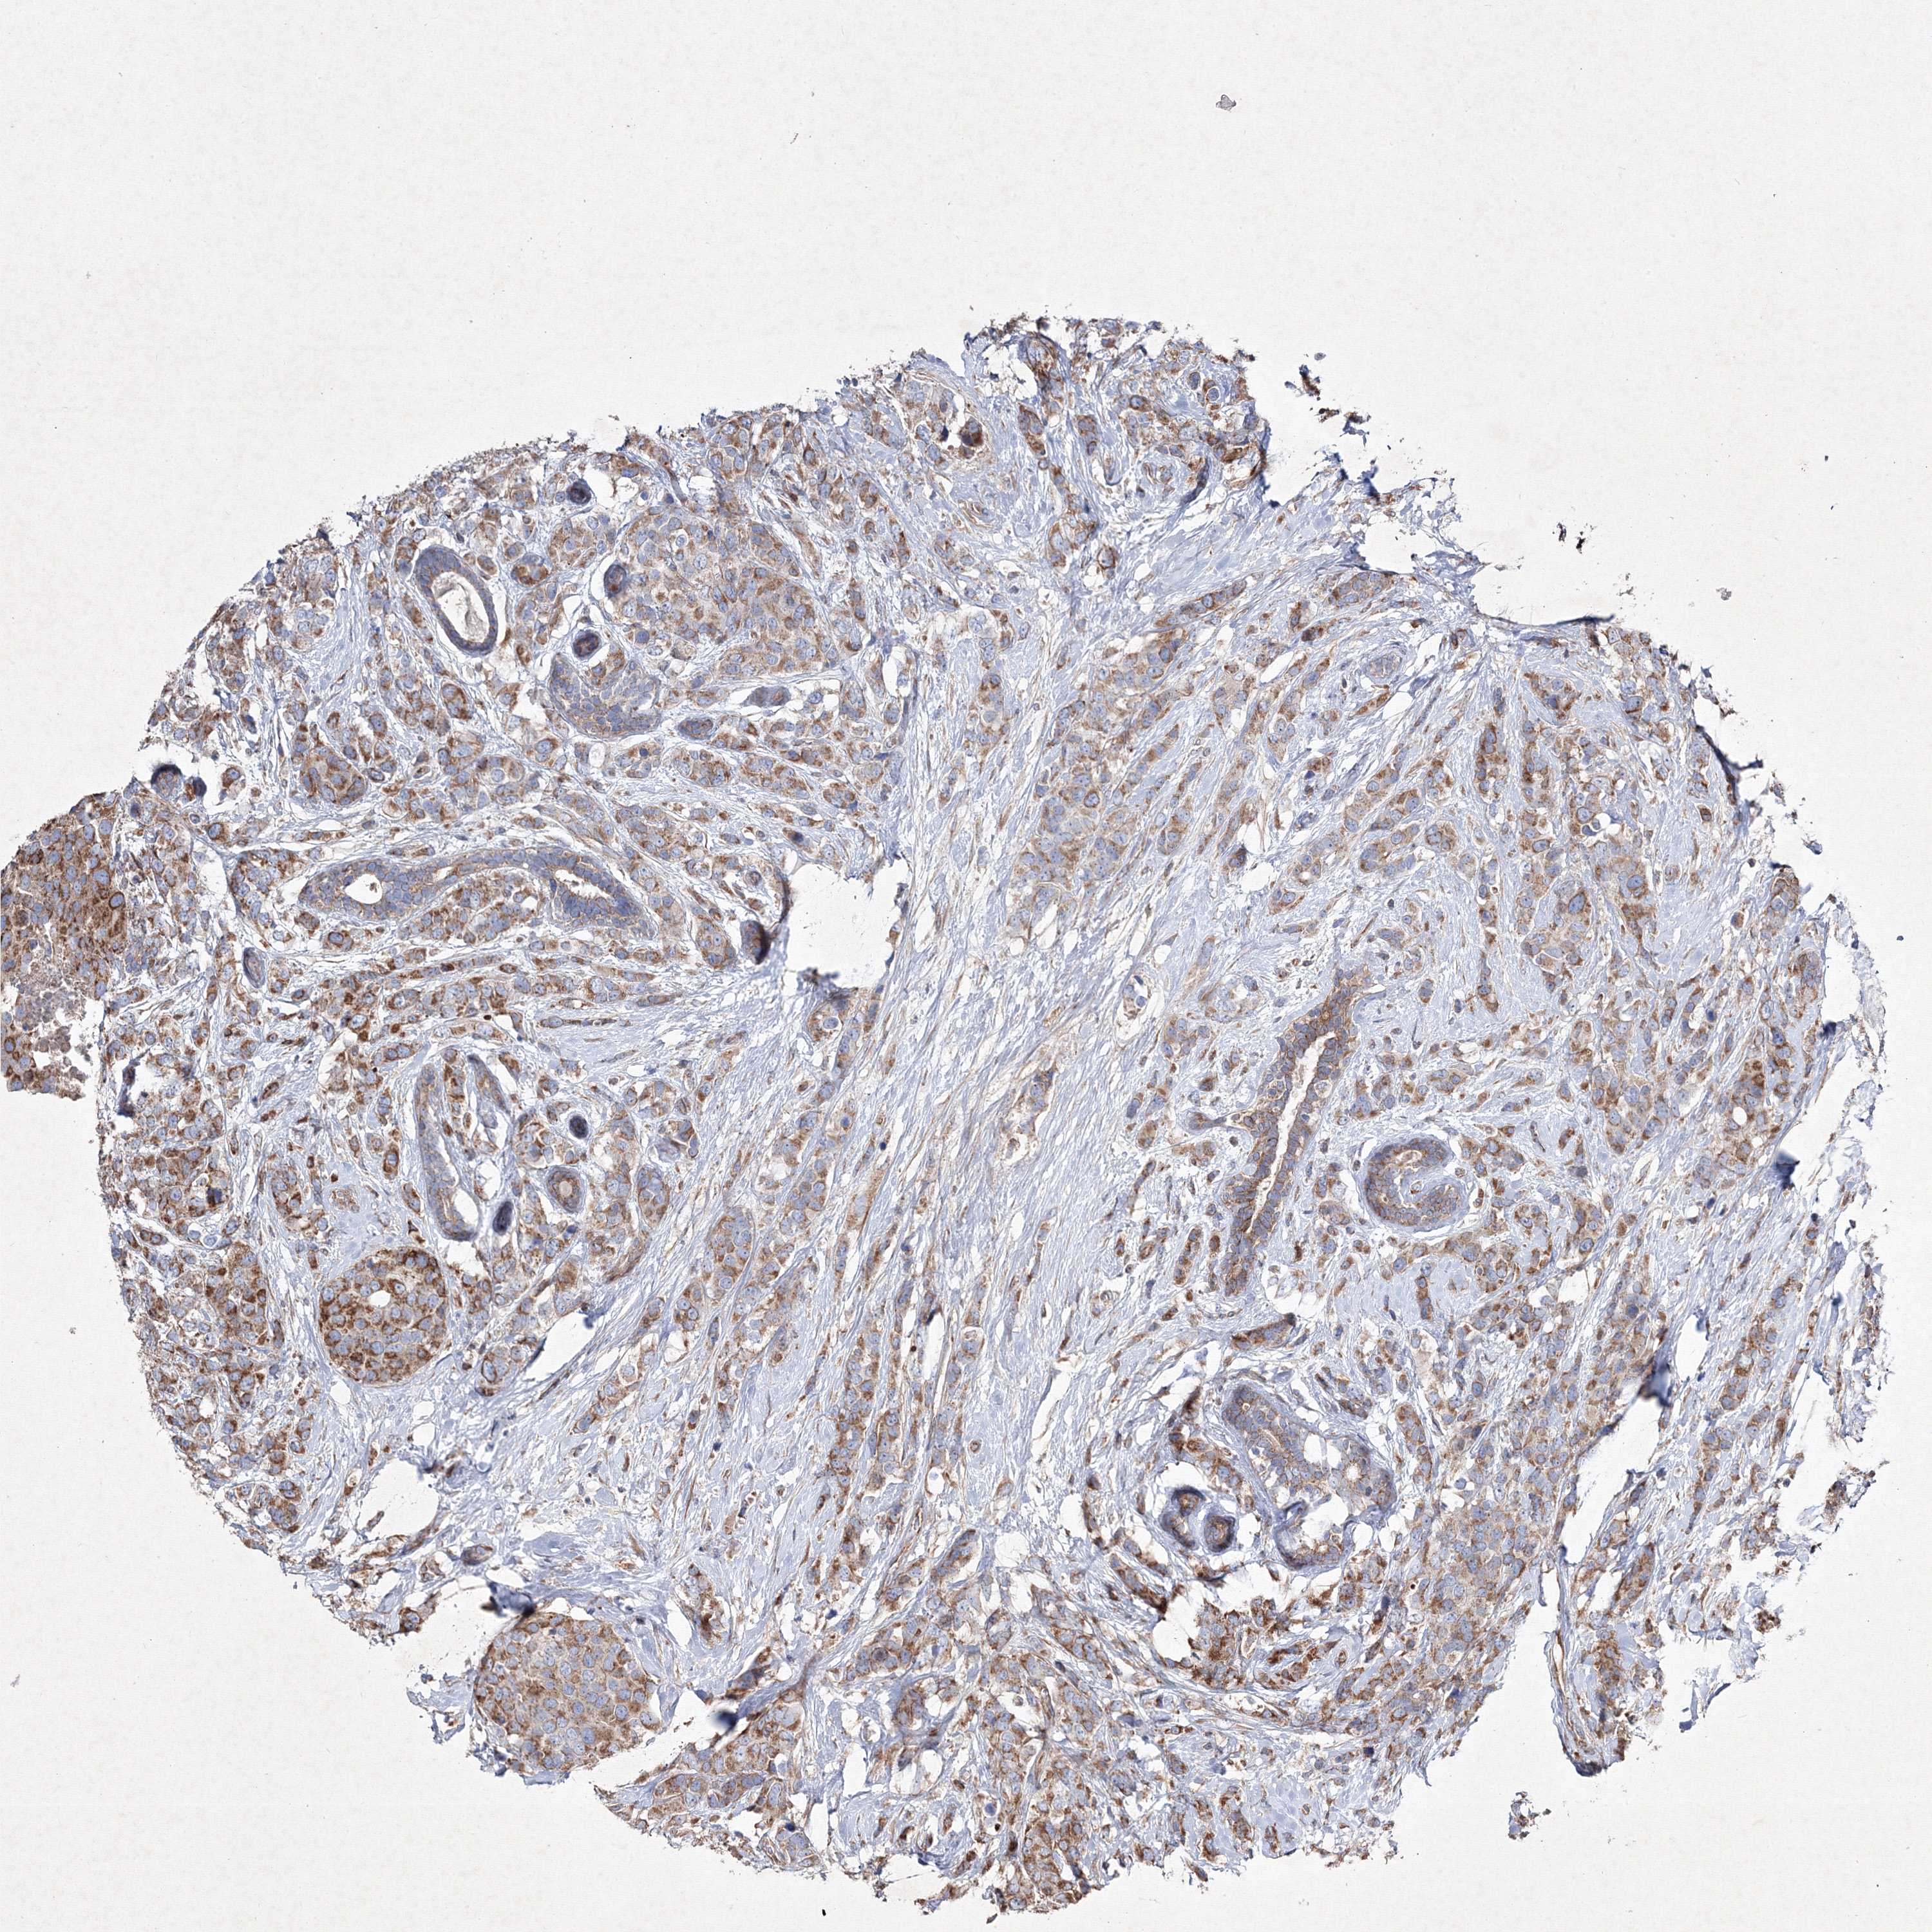

CANCER BREAST CANCER Show tissue menu

BRCA TCGA BRCA VALIDATION PROTEIN EXPRESSION

Breast cancer

Human cancer

Breast invasive carcinoma